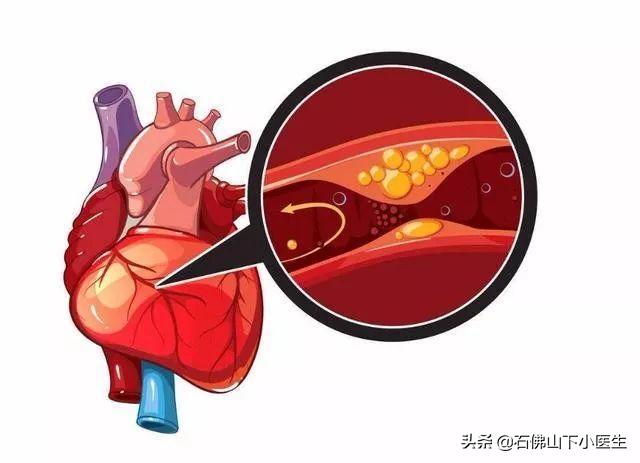

でもね。もし冠動脈の内腔が狭くなっていれば、心筋の酸素需要が増大しても、冠動脈の血液供給はそれに応じて増大することができず、心筋虚血となり、心筋虚血が長引くと心筋壊死を引き起こし、心臓発作の引き金となる。急性心筋梗塞は、不整脈、心原性ショック、心不全、心室壁破裂などの重篤な結果をもたらすこともあるので、冠動脈性心疾患は非常に深刻に受け止めなければならない。

冠状動脈は心臓に血液を供給する主な動脈で、年齢、三高、慢性病、悪習慣などの影響を受けて、心臓に血液を供給する冠状動脈も他の動脈と同じように、アテローム性動脈硬化症、狭窄、プラークなどの問題が現れる、冠状動脈の狭窄が50%以上の場合、通常、心臓の血液供給と酸素供給が大きな影響を受けると考えられ、このような場合、冠状動脈性心臓病と診断することができます。このような場合、冠動脈性心疾患と診断することができる。

(2) 動脈硬化:冠動脈性心疾患とは、血液中の脂質成分が内皮細胞の下に侵入し、炎症反応が起こり、動脈硬化性プラークが形成されることによって引き起こされる病気のことである。

- 冠動脈は、心臓そのものに血液を供給する動脈であり、動脈硬化、または私たちがよく呼ぶプラークである。冠動脈はプラークを生成し、プラークは徐々に大きくなり、心臓への血液と酸素が不足し、さまざまな症状を引き起こす。

冠動脈性心疾患とは、冠動脈アテローム性動脈硬化性心疾患の略称であり、主に心臓に血液を供給する動脈である冠動脈のアテローム性動脈硬化によって引き起こされる。動脈にアテローム性動脈硬化症が起こると、動脈の内表面にプラークが形成され、プラークが蓄積するほど動脈の直径が狭くなる。狭窄の程度が50%未満であれば、心筋への血液供給には影響しないので、一般的に症状はありませんが、50%以上になると、心筋への血液供給に影響を及ぼし、心筋の酸素消費量が増加しても、心筋が十分な酸素を得ることができず、心筋虚血、低酸素状態になると、胸部圧迫感、胸痛の症状が誘発され、これを狭心症と呼びますが、狭心症の症状は活動を停止すると徐々に緩和されます。狭窄の程度がさらに悪化したり、局所的なプラークの破裂、冠動脈の血栓閉塞によって心筋虚血が生じたりすると、狭心症の程度はさらに悪化し、緩和されない状態が続き、閉塞が解除されなければ心筋虚血壊死を引き起こし、ついには患者の突然死に至ることもあり、これが心筋梗塞と呼ばれるものです!